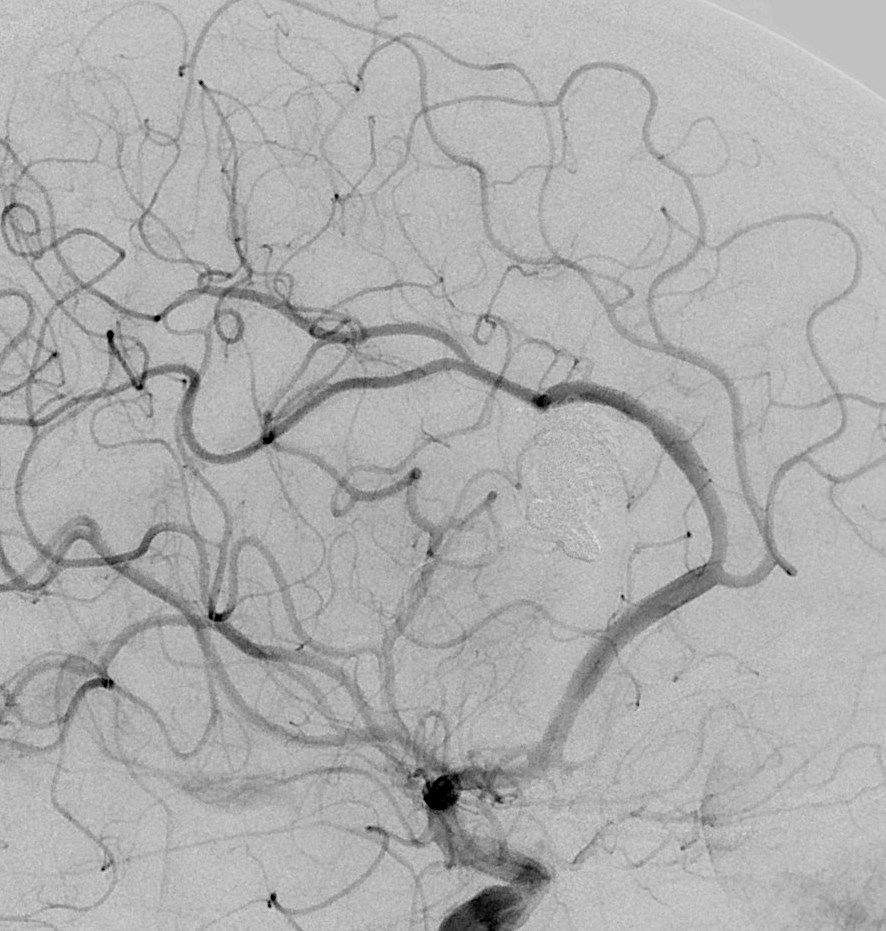

患者女性,39岁,以头痛1月余入院,患者入院前1个月无明显诱因出现头痛、头晕并呕吐,伴有短暂昏迷,当地医院头颅CT、MRI(图1),查体:未见异常。当地医院给予保守治疗,转入我院行DSA(图2)示:右侧胼胝体动静脉畸形。

图2:右侧颈内动脉造影,右侧胼胝体动静脉畸形,供血动脉为胼周动脉供应胼胝体动脉分支,引流静脉通过透明隔静脉向大脑内静脉引流及通过下矢状窦向直窦引流红色箭头为供血动脉,蓝色箭头为引流静脉。